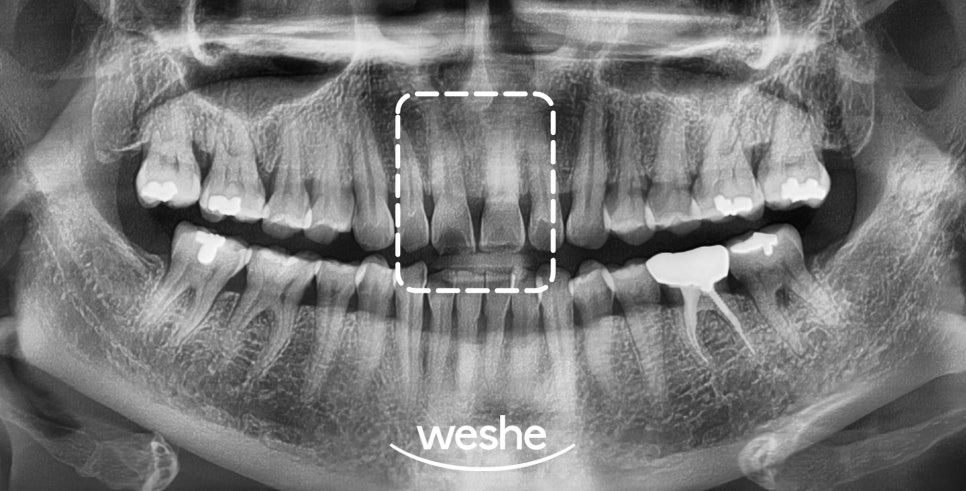

구강 내 모습을 확인해 보면

앞니 사이가 벌어져 있는 것을

확인할 수 있습니다.

그와 더불어, 아래턱 앞니 부분이

치열이 좋지 않은 것을

관찰할 수 있는데요.

이 케이스의 구강 상태를 보았을 때

문제점은 관리가 잘되지 않는

치아 배열 형태를 가지고 있어

치주질환의 진행이 용이하다는 점입니다.

검사 결과,

상악 전치부에만 공간이 있을 뿐

다른 부위는 특별한 문제가 없었습니다.